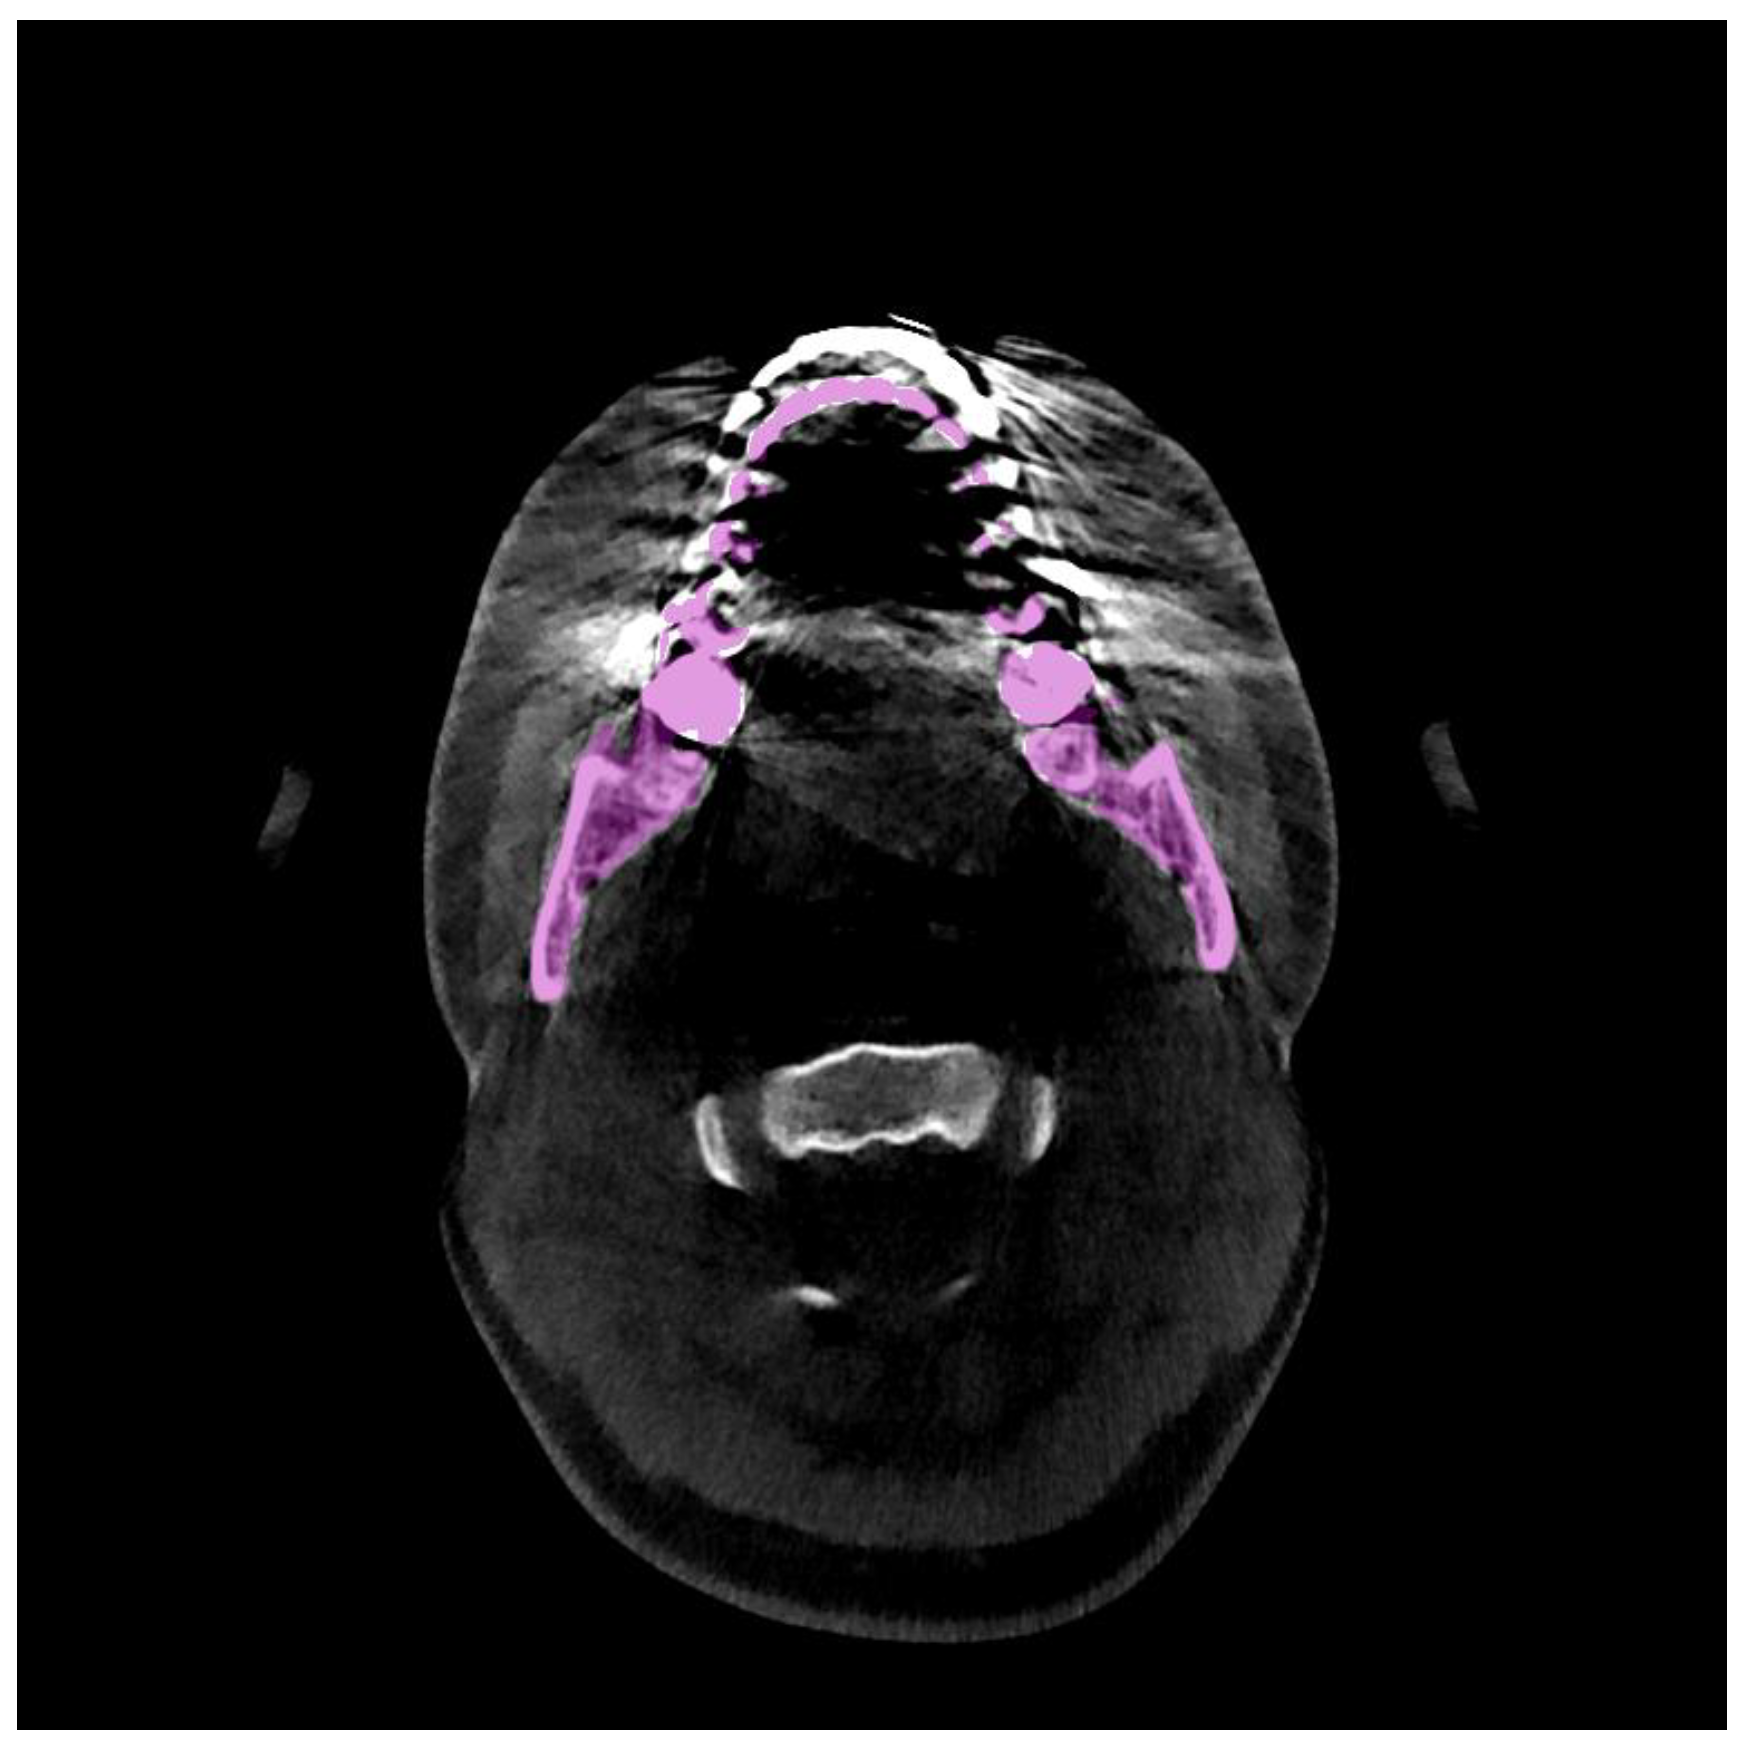

Mandible Segmentation of Dental CBCT Scans Affected by Metal Artifacts Using Coarse-to-Fine Learning Model

3.1.1. CBCT Dataset